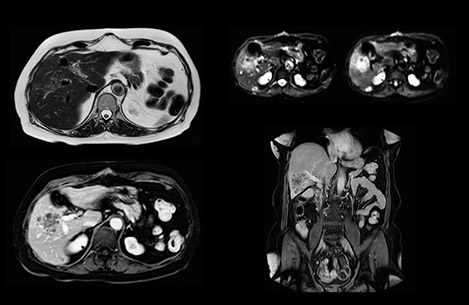

Dr. Baumann then implemented MultiVane XD for motion correction. It uses an extended reconstruction algorithm for imaging that is virtually motion free. “With MultiVane XD we get excellent motion-corrected images with high spatial resolution. We typically first optimize our scan for high image quality, and when satisfied with that, we try to reduce the scan time. So, we combined MultiVane XD with dS SENSE, which allows us to shorten the scan time,” he explains. “The performance of MultiVane XD in liver imaging is outstanding. MultiVane XD with dS SENSE is a powerful development in improving liver image quality.” “As we use breathhold imaging for T2-weighted liver scans, we depend on the patient’s ability to cooperate with the exam. This can present a real challenge when we are looking for small lesions, such as in our oncological patients. However, with MultiVane XD motion correction, we get excellent images. This is important for our surgeons, because they want to know exactly where the lesions are.”

In this example the image quality of the MultiVane XD images is evidently better than in the images without MultiVane XD. Ingenia 1.5T with dS Torso coil solution.

“Our liver exams are quite fast,” says Dr. Baumann. “If the patient tolerates it, we use an arms-up position to reduce the FOV and speed up the exam with dS SENSE.” “We acquire one transversal high resolution T2-weighted sequence with 3 mm slice thickness, for example for pancreas or liver lesions. Then we also add a T2 fat suppressed MultiVane XD SPIR sequence. We perform these two routinely in our liver imaging. We use high dS SENSE factors to significantly shorten scan times to 2-4 minutes, which can improve our protocol; it’s a very robust scan.” “We include mDIXON for the dynamic sequences because of the robust and homogeneous fat suppression we get with that. We had been using eTHRIVE, but we are now quite happy with mDIXON. Sometimes we use a medication to calm the bowels, to further improve the image quality.”